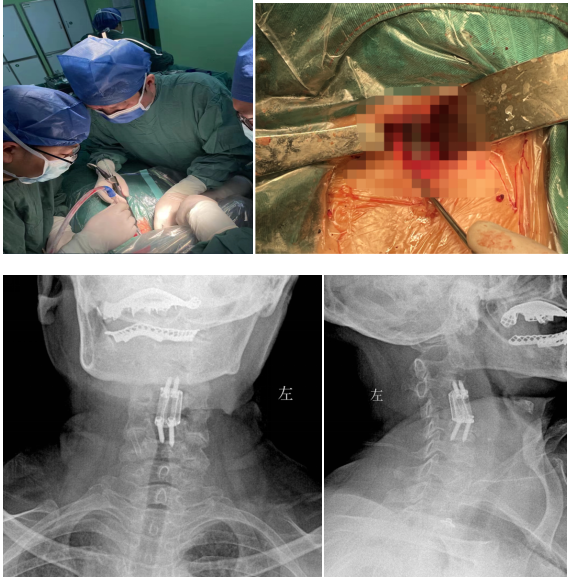

經(jīng)過周密細(xì)致的術(shù)前討論,脊柱外科團(tuán)隊最終決定為該患者擬行頸椎病灶清除、椎管減壓+植骨融合術(shù),考慮患者高齡,又有骨質(zhì)疏松,為更好保障重建穩(wěn)定性,采用3D打印進(jìn)行術(shù)前規(guī)劃設(shè)計假體進(jìn)行植入,此款融合器是國內(nèi)首款SLM激光打印融合器,具有解剖匹配、骨融合確切等優(yōu)勢,為取得優(yōu)良手術(shù)效果打下了堅實基礎(chǔ)。

經(jīng)過多學(xué)科會診(MDT),完善術(shù)前相關(guān)準(zhǔn)備后,由蘇光輝主任主刀,帶領(lǐng)團(tuán)隊錢軍、鄧三東等,精準(zhǔn)完成病灶清除、椎管減壓、植入3D打印cage等流程,在麻醉師、手術(shù)室的全力配合下,整臺手術(shù)一氣呵成,手術(shù)順利。